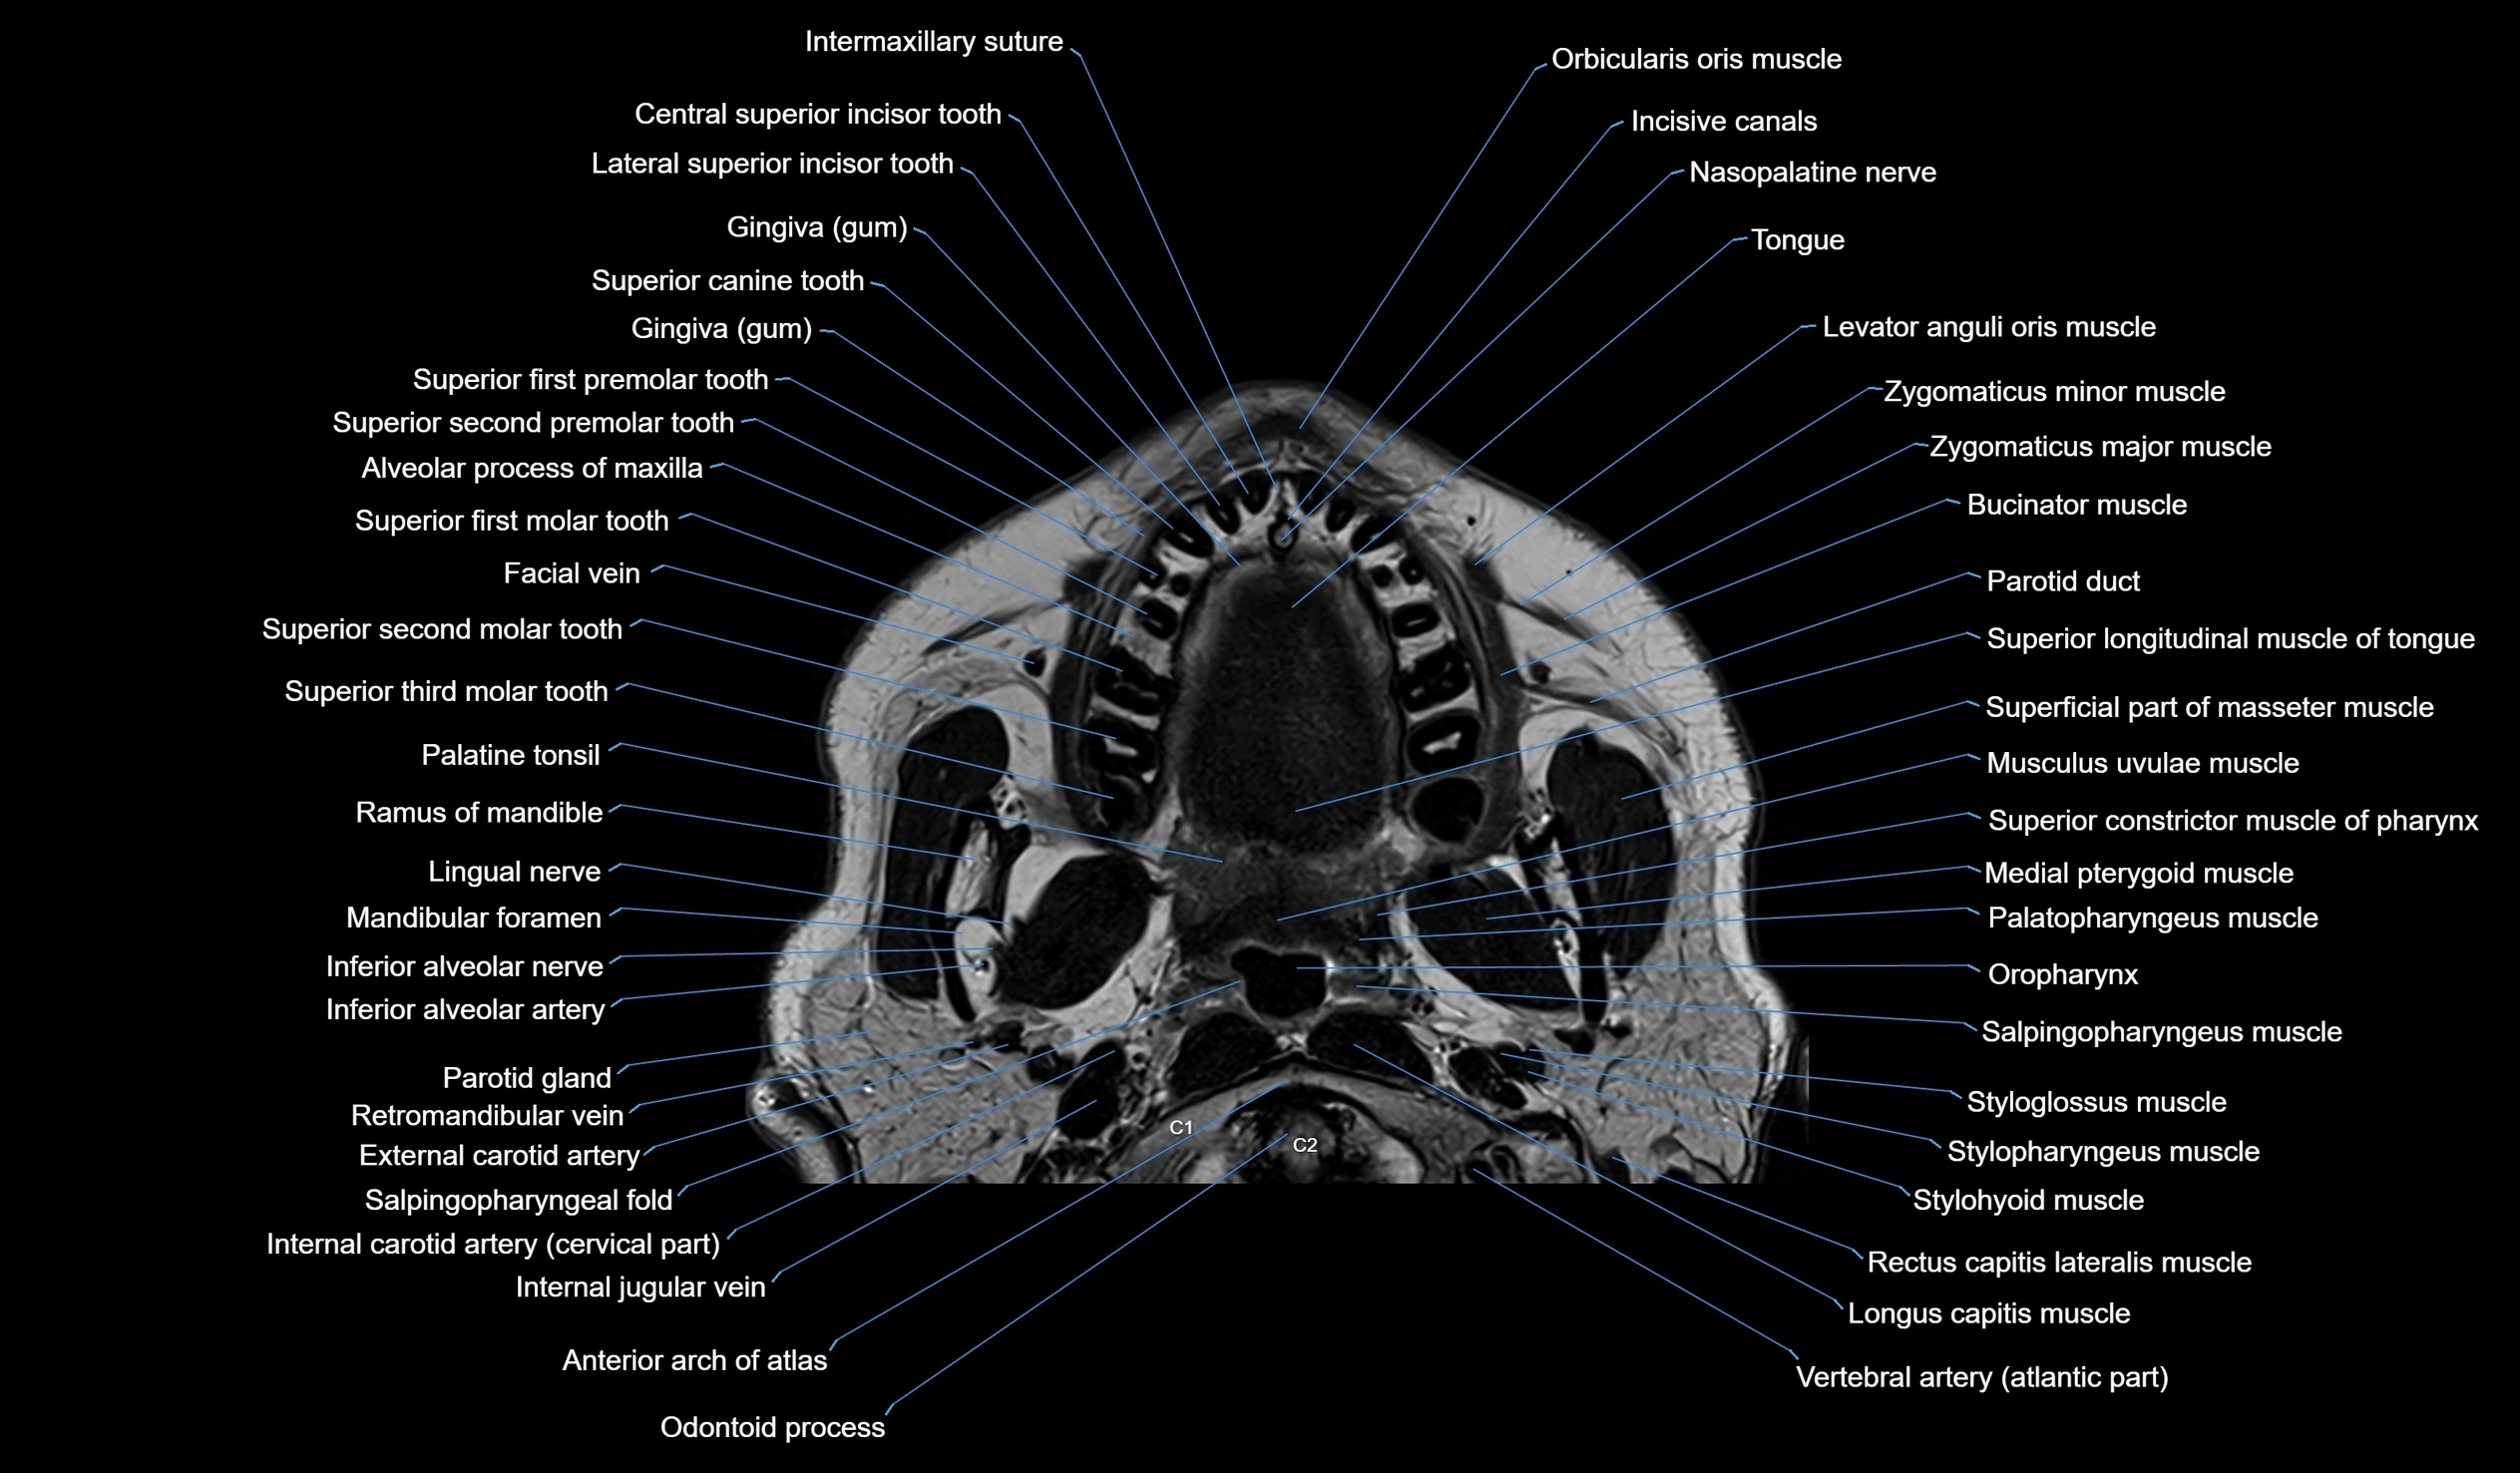

MRI images